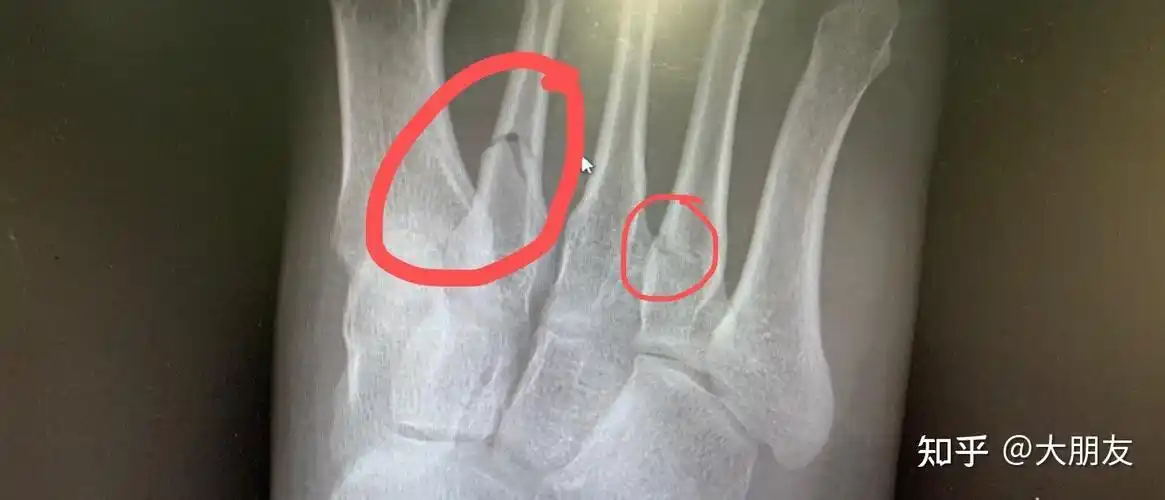

脚趾骨折,哪位帮看看用不用治疗

右脚第二第四跖骨(脚趾骨)骨折0101

看个足部的片子